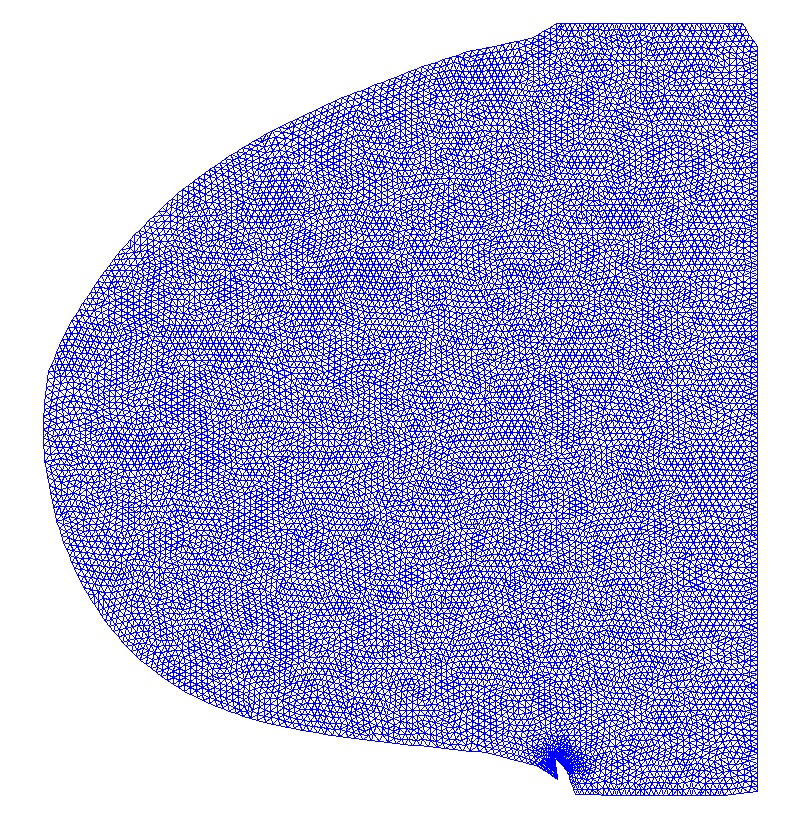

To reduce computational cost and get even more accurate results, we may create a Finite Element (FE) grid on the area of interest rather than on the image boundaries. For illustration, we consider the MR-images and shown on the top/left and bottom/left of Fig. 4, respectively. We automatically produce a mesh on the breast boundaries (see on the left of Fig. 5). The segmentation for and for is shown on the center and right of Fig. 5, respectively.

This FE approach can be easily adapted to other images, for example in Fig. 6 left, we apply this approach for segmenting a ventricle MRI heart image, taken from Angenent2006 with permission from1. In the center of Fig. 6, the FE mesh is shown and on the right of the figure, we see the segmentation of the adaptive eigenspace using FE. As discussed in Rem. 1, we do not always get a binary segmentation, but this is easy to get using a standard threshold.